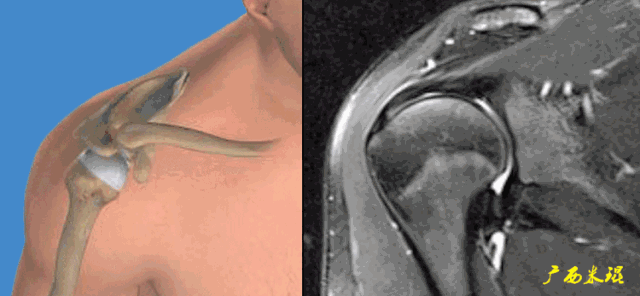

(1)肩峰撞击

肩峰撞击由Neer于1972年提出,肩峰下关节由于解剖结构原因或动力学原因,在肩的上举、外展活动中,因肩峰下组织发生撞击而产生的症状。肩峰撞击与肩袖损伤互为因果,是肩关节MRI诊断的重中之重!

肩峰撞击并非仅指肩峰,撞击部位可以在肩峰前1/3前下面、喙肩弓、肩锁关节下面以及喙突,对应面是大结节、小结节,MRI阅片中要重点关注这些结果以及夹于其中的肩袖组织。

(3)肱二头肌长头腱病变

肱二头肌长头腱与肩袖关系极为密切,其肌腱炎、肌腱滑脱等改变很多情况下是伴随肩袖损伤而来的。当我们在MRI上发现肱二头肌长头腱的严重病变,应该也要考虑到有肩袖损伤的可能。

总之,大家一定要记住:肩袖损伤永远不会是一种孤立的单纯的损伤!MRI诊断中应该紧紧抓住这个特点才能更准确、更全面地进行诊断!